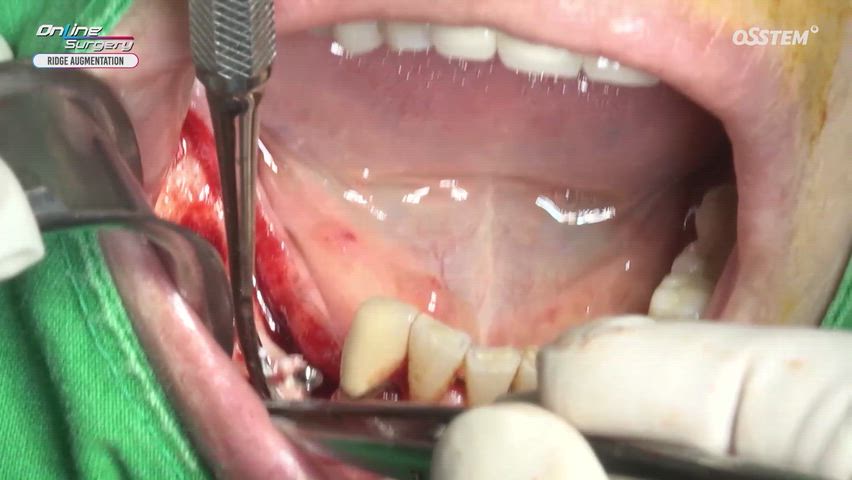

Mandibular vertical ridge augmentation using OssBuilder a...

Online Surgery

Views 6